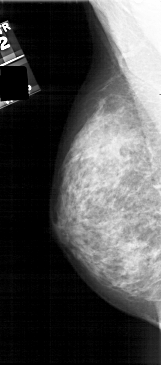

A_1808_1.LEFT_CC

LEFT_CC LINES 4801 PIXELS_PER_LINE 2296 BITS_PER_PIXEL 12 RESOLUTION 43.5 NON_OVERLAY

FILE: A_1808_1.RIGHT_CC.OVERLAY

TOTAL_ABNORMALITIES 1

ABNORMALITY 1

LESION_TYPE MASS SHAPE IRREGULAR MARGINS ILL_DEFINED

ASSESSMENT 4

SUBTLETY 2

PATHOLOGY BENIGN

TOTAL_OUTLINES 1

BOUNDARY